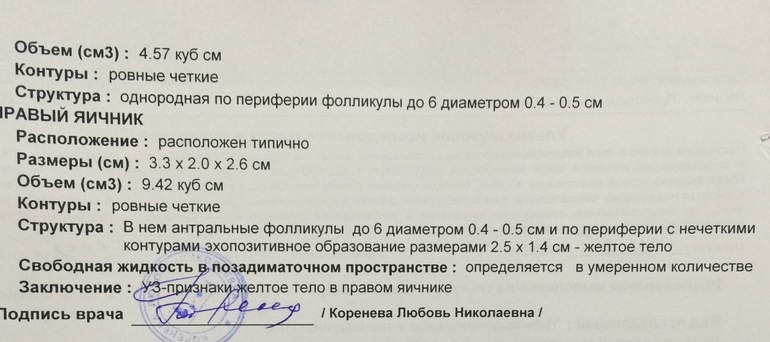

Девчата ,а вот и я с результатами узи!!немного в шоке )))в прошлый цикл через 5 дней после овуляции жт уже почти не видно было и эндик уменьшился .Сейчас я ходила не к своей узистке в другую больницу (но она не из дешёвых ).В общем эндик 10 -11 (сразу после овули он был 11) и жт 25!!(а было 20-21 после овуляции )Сегодня 8 дпо и что думаете на этот счёт?все-таки шанс есть??

Как мне говорила Г при беременности желтое тело расцветает) так что все шансы!!!! Ждем эвик на 10 дпо)

Что-то принимали, чтобы жт 25 мм стало? У меня сегодня тоже было УЗИ, жт 13, было 10 мм.